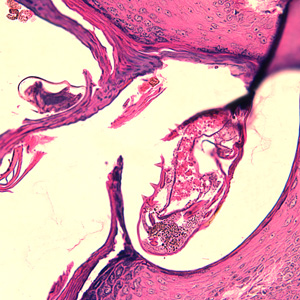

Case #244 – January, 2009

An 80-year-old resident of a long-term care facility presented with a skin condition manifesting as thick crusts over the skin accompanied by slight itching. The patient was originally treated for impetigo, with no resolution, and was ultimately admitted to the hospital for further testing. A skin biopsy was performed. The specimen was sectioned, stained with hematoxylin and eosin (H&E) and sent to a dermatopathologist for diagnostic assistance. Figures A–D show what was observed in the stained sections. Figures A and B were taken at 200x magnification. Figures C and D represent the same fields, respectively, taken at 400x magnification. What is your diagnosis? Based on what criteria?

Figure C